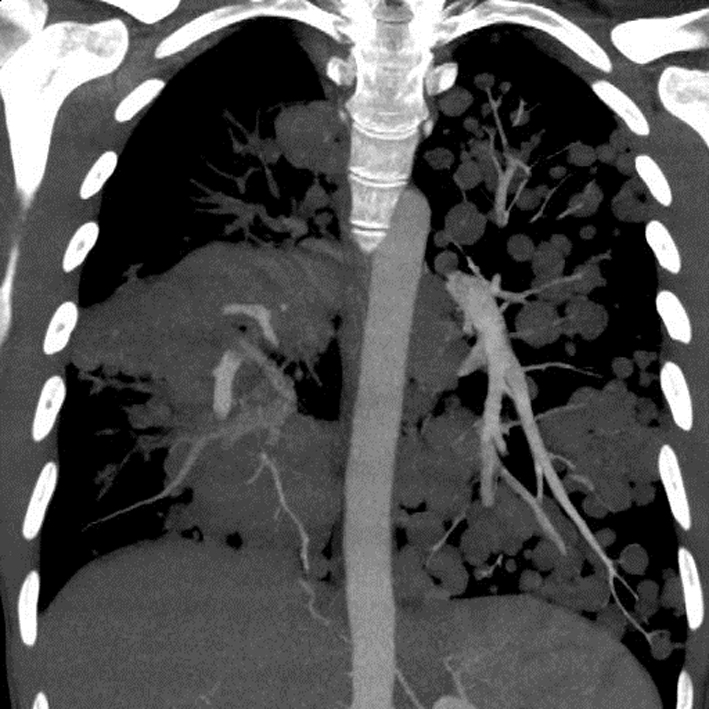

A chest X-ray (Fig. 1) was obtained and showed the presence of multifocal rounded airspace opacities within both lungs. Subsequently, a CT scan of the chest (Fig. 2, 3) was obtained which demonstrated bilateral pulmonary emboli along with bilateral conglomerate pulmonary nodules in both lower lungs.

![]() Click for large image | Figure 2. Coronal section of CT chest showing bilateral cannonball pulmonary nodules. |

Based on patient’s history of IV drug abuse, recent episode of cellulitis, concomitant lower back pain and consistent imaging findings, the diagnosis of right-sided infective endocarditis with septic pulmonary embolism was initially considered and patient was empirically started on IV antibiotics after drawing blood cultures. However, a transthoracic echocardiogram obtained the next day did not reveal any vegetations and the patient continued to remain afebrile with all blood cultures coming back negative. This prompted a reconsideration of the diagnosis. All radiographic images were reviewed again with radiology and were notable for the lack of necrosis in the pulmonary nodules. A follow-up abdominal CT also revealed the presence of retroperitoneal lymphadenopathy indicating a possible neoplastic process.

In rare cases, patients may present with symptoms from the metastasis. In these patients, a careful physical examination is of prime importance in pointing towards the correct diagnosis. Radiological features such as multiple lung nodules greater than 1 cm in size seen on a plain chest radiograph are also usually indicative of disseminated malignancy to the lungs [5, 6]. Such large, rounded “cannonball” nodules are associated with poor prognosis [7, 8].